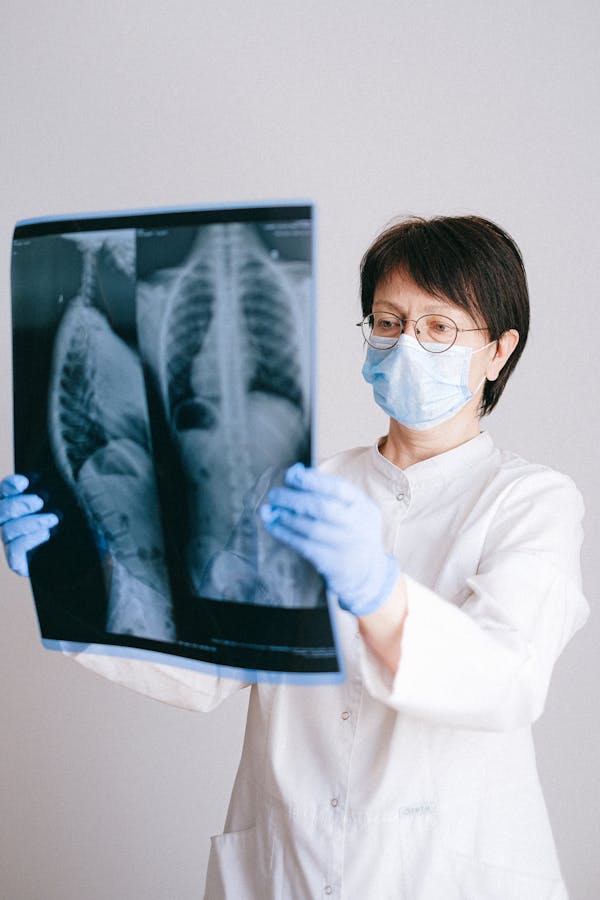

Ultrasound

High-resolution diagnostic ultrasound scanning for abdominal, pelvic, obstetric and small parts imaging.

Diagnostic Ultrasound System

High-resolution real-time ultrasound scanner for abdominal, pelvic, and obstetric imaging.

Next-Level Imaging Technologies

We are expanding our imaging capabilities. Advanced CT Scan and MRI services are arriving soon to provide even more comprehensive diagnostic options.